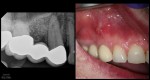

Entire buccal plate missing. CBCT at 5 years suggests most, but not all, bone has regenerated. As canine bridge abutment, it is subjected to some occlusal trauma. gbc